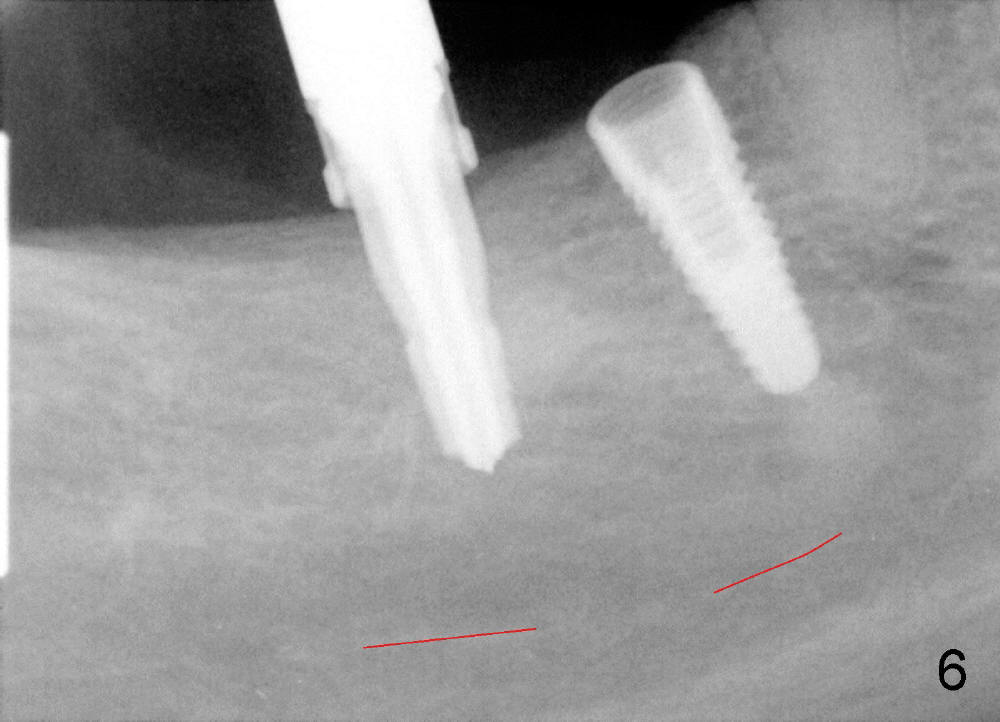

PA is retaken after placement of a submerged (SM) implant (4.5x12 mm) at #30 and insertion of 4.5x10 mm drill at #31(Fig.6).